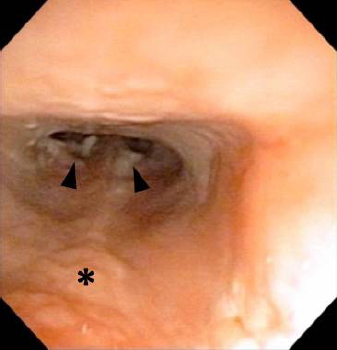

On day 1, the complete blood count, blood biochemical analysis, and radiographic examination for the skull revealed no specific abnormalities. A thoracic ultrasound identified hypertrophic cardiomyopathy (HCM), while an abdominal ultrasound did not find any masses and lesions suspicious of neoplasm. To further elucidate the cause of nasal signs, head, chest, and abdominal CT and rhinoscopy were carried out on day 1 under general anesthesia. Head CT in the transverse plane revealed that the nasal cavity was filled with soft tissue material suspicious of nasal discharge (Fig. 1a), and the frontal sinus was partly filled with the same material (Fig. 1b). There were no contrast effects in either area (Fig. 1a and b). Head CT in the mid-sagittal plane revealed slight nasopharyngeal swelling in the dorsal portion, but there were no abnormal contrast effects, osteolytic changes, or lymphadenopathies (Fig. 1c). Chest and abdominal CT did not show any lymphadenopathies and masses in the body. After the nasal cavity was cleansed with saline several times, it was examined by anterograde and retrograde rhinoscopy. Anterograde rhinoscopy found only a little nasal discharge, while retrograde rhinoscopy detected a little nasal discharge and slight swelling of the nasopharyngeal mucosa but without masses (Fig. 2). Several biopsy specimens were obtained from the nasopharyngeal mucosa’ swollen sites with endoscopic biopsy forceps for histopathological and immunohistochemical analyses. The histopathological and immunohistochemical specimens were reviewed by a single board-certified veterinary anatomic pathologist (H.K.). The collected nasal discharge was subjected to bacterial culture and antimicrobial susceptibility tests. To prevent rhinoscopy-associated infection and bleeding in the nasal cavity, the cat was subcutaneously injected with enrofloxacin (Baytril; Bayer, Tokyo, Japan, 5 mg/kg q24h), carbazochrome (Adona; Nipro ES Pharma, Osaka, Japan, 1 mg/kg q12h), and tranexamic acid (Vasolamine; Meiji Seika Pharma, Tokyo, Japan, 10 mg/kg q12h) on day 1. The cat was orally administered with the same drugs on days 2 and 3 with slight modifications as follows: carbazochrome (Adona; Nipro ES Pharma, 0.5 mg/kg q12h) and tranexamic acid (Transamin; Daiichi Sankyo, Tokyo, Japan, 10 mg/kg q12h). Also, because the cat had HCM, oral administration of carvedilol (Artist; Daiichi Sankyo, 0.05 mg/kg q24h) was initiated on day 2.

Fig. 2. Retrograde rhinoscopy for the nasopharynx. Nasal discharge (arrowheads) and slight swelling of the nasopharyngeal mucosa (asterisk) were detected.